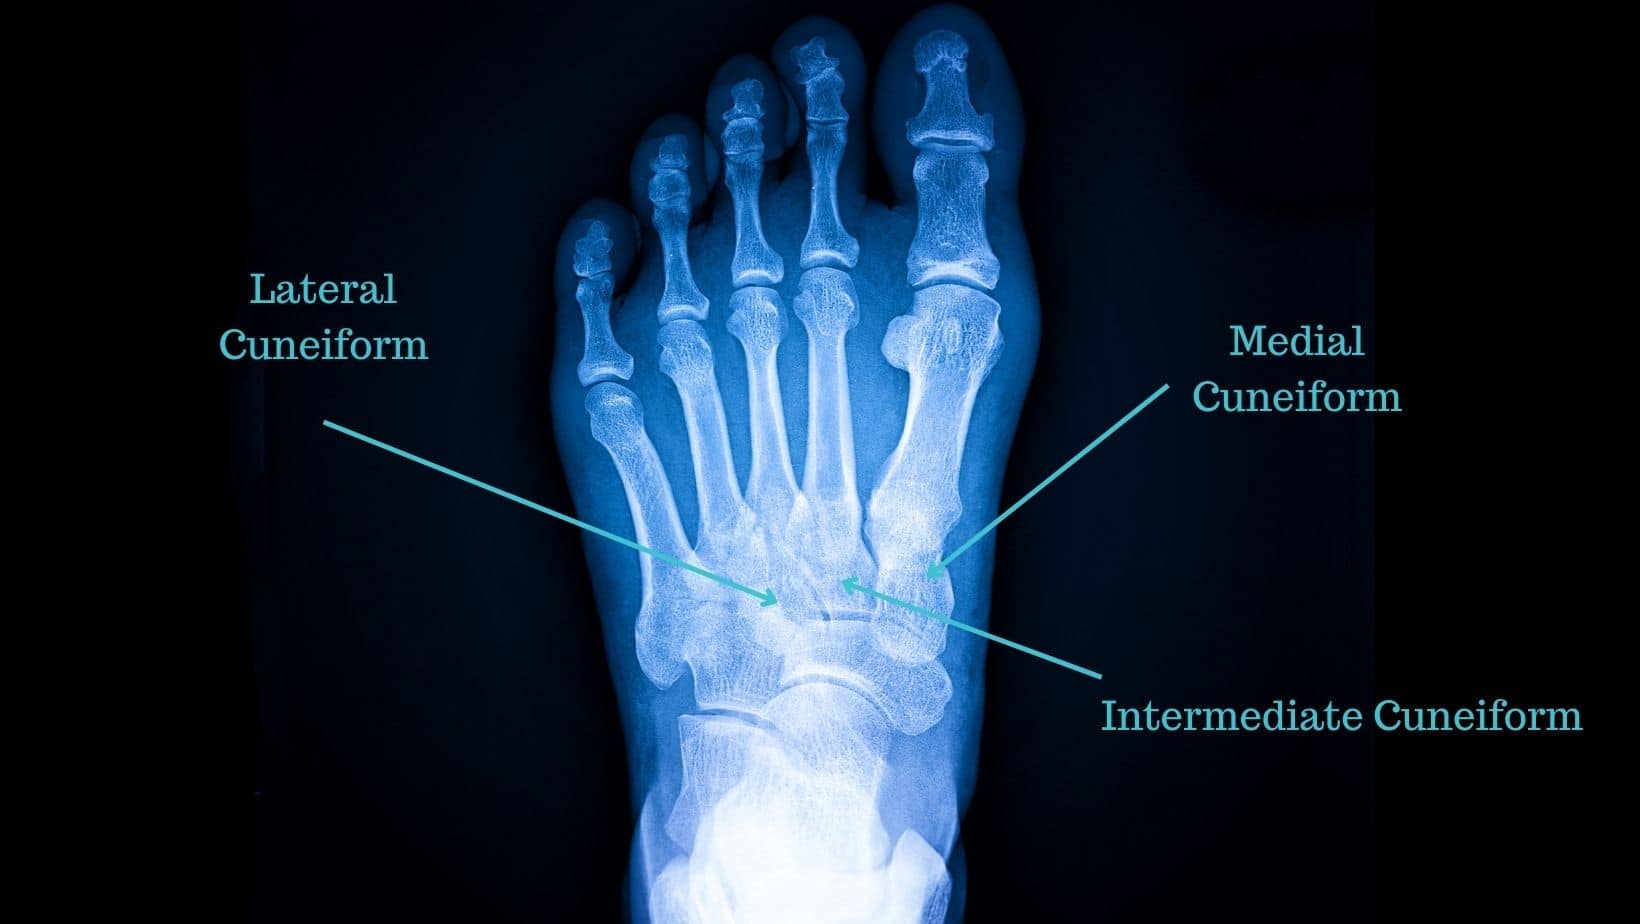

Foot Bones Lateral. And the forefoot contains the. the three cuneiforms (lateral, intermediate (or middle) and medial) are wedge shaped bones. The intermediate tarsal bone is the navicular. It can make standing, walking, or running painful. These bones are numbered from one to five, starting with the first metatarsal beneath the big toe and moving laterally towards the fifth metatarsal beneath the little toe. the metatarsal bones are a group of five long bones located in the metatarsus of the foot, between the tarsal bones (near the ankle) and the phalanges (toe bones). The midfoot contains the rest of the tarsal bones; lateral foot pain happens on the outer edges of your feet. the hindfoot is composed of 2 of the 7 tarsal bones, the talus, and the calcaneus; The proximal tarsal bones are the talus and calcaneus. learn the bones of the foot in half the time with these interactive quizzes and labeling activities! Several things can cause lateral foot pain, from exercising too much to birth. They articulate with the navicular posteriorly,. These are three highly mobile bones (medial, intermediate, and lateral) that make up the actual arch of the foot. The distal tarsals are the cuboid and three cuneiform bones (lateral, intermediate, and medial).